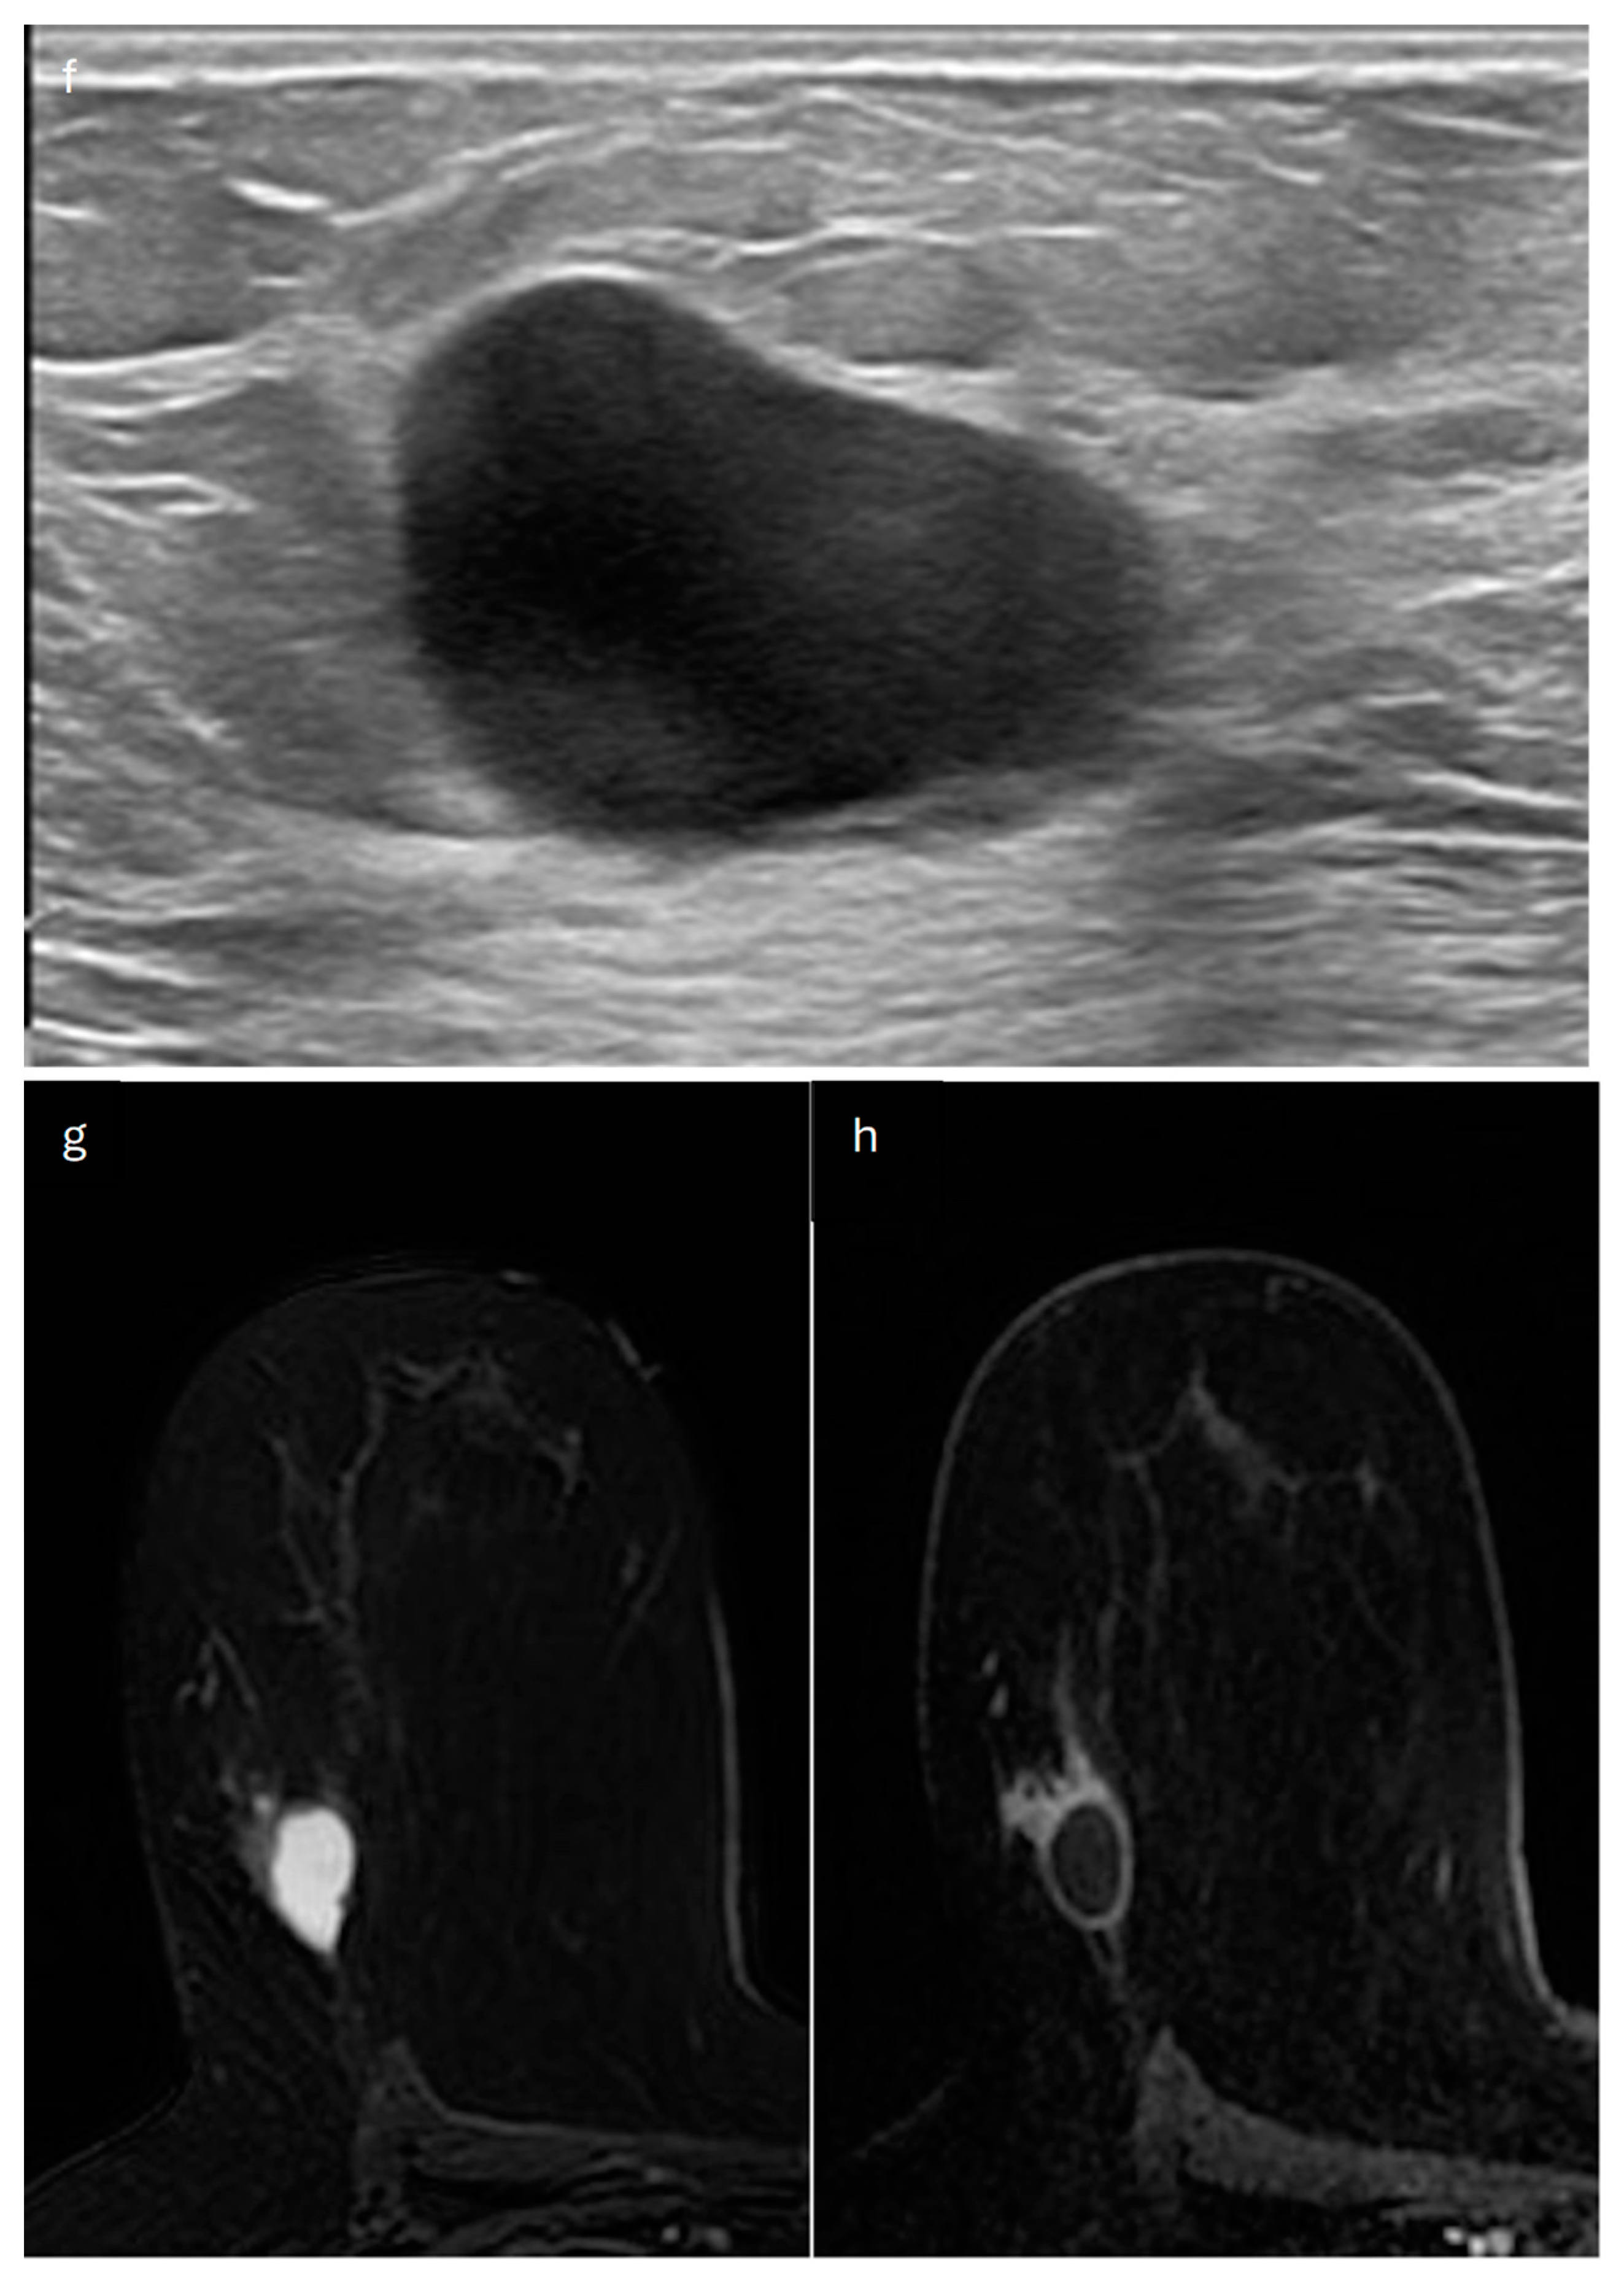

4. Mucinous